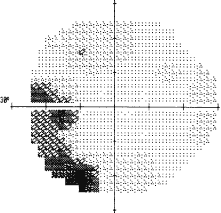

There are several well-described complications that may occur after macular hole repair. Acute complications include retinal tears76 and endophthalmitis.77,78 Long-term complications include nuclear sclerotic cataract in the vast majority of phakic patients,79 and retinal detachment in 1% to 3% of patients.77,78 In addition, there is a 2% to 10% risk of a repaired macular hole reopening at a later date.80–82 Less frequent surgical complications that have been reported include enlargement of the hole,77 photic toxicity or retinal pigment epithelial alterations,83,84 exudative retinal detachment,85 glaucoma,86 proliferative vitreoretinopathy,87 and dense wedge-shaped temporal visual field defects (likely resulting from dehydration injury during fluid-air exchange, Fig. 9).88,89

Fig. 9. Humphrey visual field of a left eye following surgical repair of macular hole. Note the dense defect in the inferotemporal quadrant.